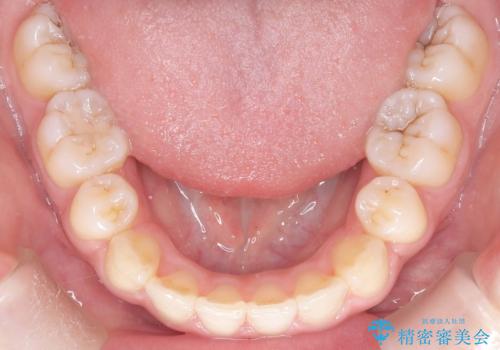

- 「歯のでこぼこと捻じれを治したい」を主訴に来院された患者様です。矯正検査の結果、上顎前歯がかなり唇側傾斜という結果になったので上下左右4番を抜歯をしワイヤー矯正で治療を行いました。

抜歯矯正でしたが順調に治療が進み2年で矯正治療を終えることが出来ました。歯のでこぼこや捻じれが治り、口元も下がって患者さんも大変満足されていました。